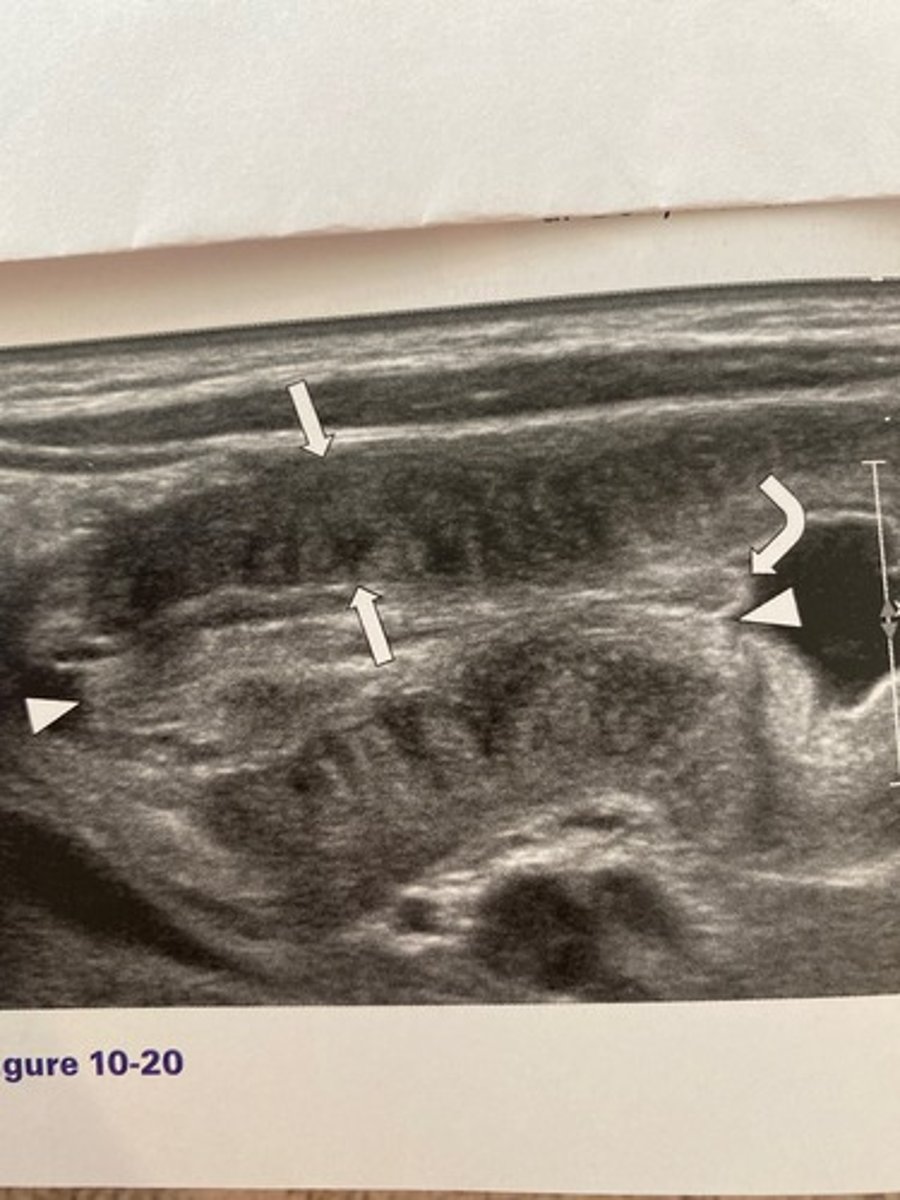

The measurement identified by the arrows in

Figure 10-20 should not exceed:

a. 2 mm.

b. 3 mm.

c. 3.5 mm.

d. 6 mm.

What is the most common age range at which the abnormality occurs in Figure 10-20?

a. 5 to 10 years of age

b. 1 to 4 weeks of age

c. 3 months to 3 years of age

d. 2 to 6 weeks of age

What is the sonographic sign noted in Figure

10-20?

a. Doughnut sign

b. Pyloric sign

c. Cervix sign

d. Cinnamon-bun sign

What would be the least likely clinical finding associated with Figure 10-20?

a. Weight gain

b. Olive sign

c. Projectile vomiting

d. Dehydration

What are the diagnostic criteria for pyloric stenosis?

a. 17 mm in thickness and 2 mm in length

b. 17 mm in thickness and 3 mm in length

c. 3 mm in thickness and 10 mm in length

d. 3 mm in thickness and 17 mm in length